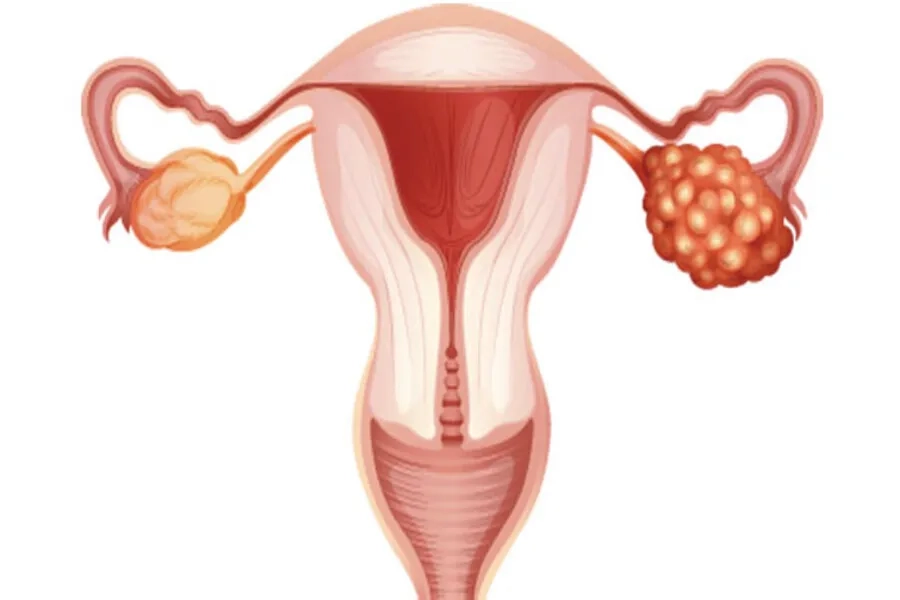

Hiệu quả IUI phụ thuộc nhiều vào tình trạng tử cung và chất lượng nang trứng. Nội mạc tử cung cần đủ tốt và từ 1-2 nang trứng đạt tiêu chuẩn về kích thước vào ngày kích thích rụng trứng. Với phụ nữ mắc lạc nội mạc tử cung nặng, tổn thương ống dẫn trứng hoặc tinh trùng bất thường nặng có thể làm giảm hiệu quả của IUI, khi đó IVF thường là lựa chọn ưu tiên.

Chất lượng nang noãn là yếu tố quan trọng hỗ trợ tăng cơ hội thụ thai

Trong trường hợp IUI thất bại nhiều lần, hoặc nếu người chồng có tinh trùng yếu, tinh trùng ít hoặc dị dạng, người vợ bị tắc ống dẫn trứng hoặc tuổi trên 40, bác sĩ thường tư vấn các kỹ thuật hỗ trợ sinh sản khác như: thụ tinh trong ống nghiệm (IVF), tiêm tinh trùng vào bào tương noãn (ICSI).